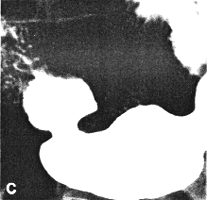

Six months later, after proper diabetic control, he had improved clinically. On this occasion the stomach contained less residual food. Shallow gastric peristaltic waves were present, while the pyloric sphincteric cylinder remained partially contracted throughout the examination (Fig. 37.1C). Although this was less marked than on the previous occasion, normal cyclical activity remained absent and no maximal or complete contractions were seen. Peristaltic activity in the duodenum appeared to be decreased. Active peristaltic contractions with a fast passage of barium was noted in the jejunum. The films also showed scattered areas of calcification in the pancreas and the case was diagnosed as diabetic gastroparesis and chronic alcoholic pancreatitis. Case 37.2. T.M., 64 year old female with longstanding insulin-dependent diabetes mellitus and psychotic symptoms, was admitted with epigastric pain and episodes of vomiting. Radiological examination showed a decrease in frequency and intensity of gastric peristaltic waves; there was a lack of cyclical contraction and relaxation of the pyloric sphincteric cylinder, which remained in a state of partial contraction throughout the examination; this was associated with a patulous pyloric orifice measuring 1.2 cm in diameter. Sonographically the gall bladder, liver, spleen, kidneys and aorta were normal. The pancreas could not be visualized owing to obesity.

| Fig. 37.1. C-F. Case D.R. After treatment and clinical improvement. Lessened contraction of sphincteric cylinder. Some movement evident but normal cyclical activity absent. Note pancreatic calcification | |